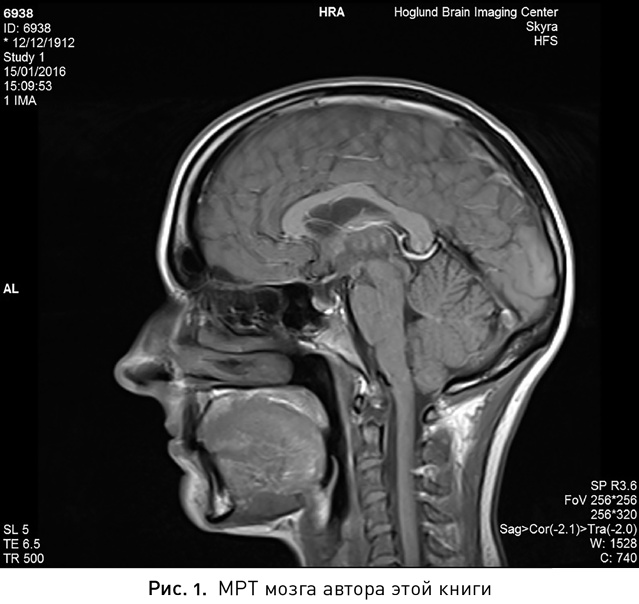

Иллюстрация к книге — Мой продуктивный мозг. Как я проверила на себе лучшие методики саморазвития и что из этого вышло [i_002.jpg]